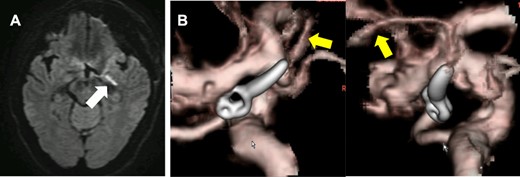

Although a complete aneurysm clipping preserving these branches was not feasible, it is also known from a report by Ihm et al. [1] that an incomplete neck clipping of a recurring aneurysm has a higher risk of recurrence. The authors performed temporary occlusion of these small branches under MEP monitoring to determine whether it was possible to sacrifice any of these perforators arising from the aneurysmal dome. MEP recording was performed every 1 min with no MEP amplitude change up to 10 min after temporally clipping of the perforators (Fig. 3).

The MEP did not change even after 10 min of occlusion and until completion of skin closure. (A; after skin is closed, B: after 10 min of occlusion, C; before occlusion of Ach A branches).